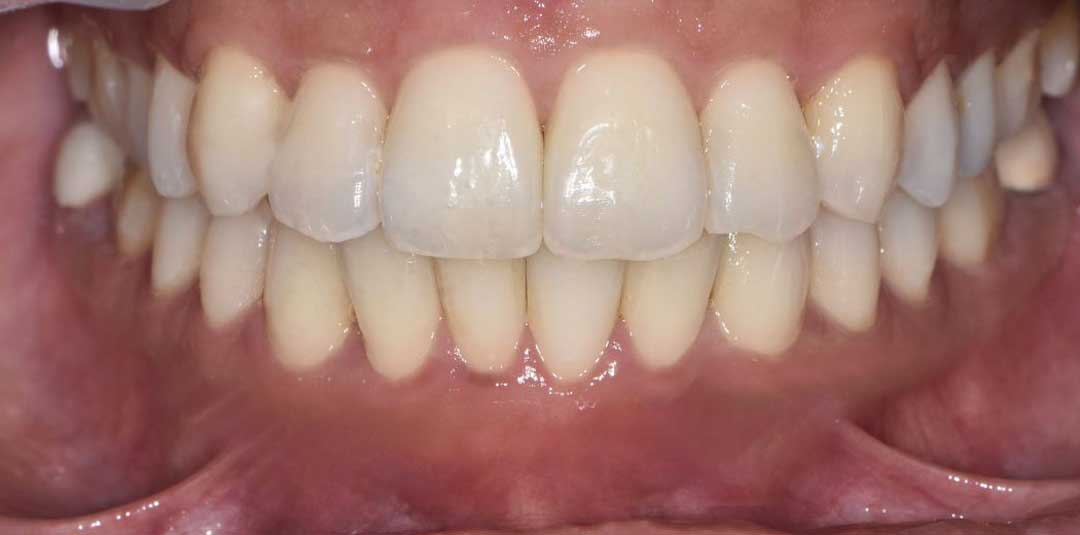

Beautiful Smiles

by Dr. Paolo Bellini